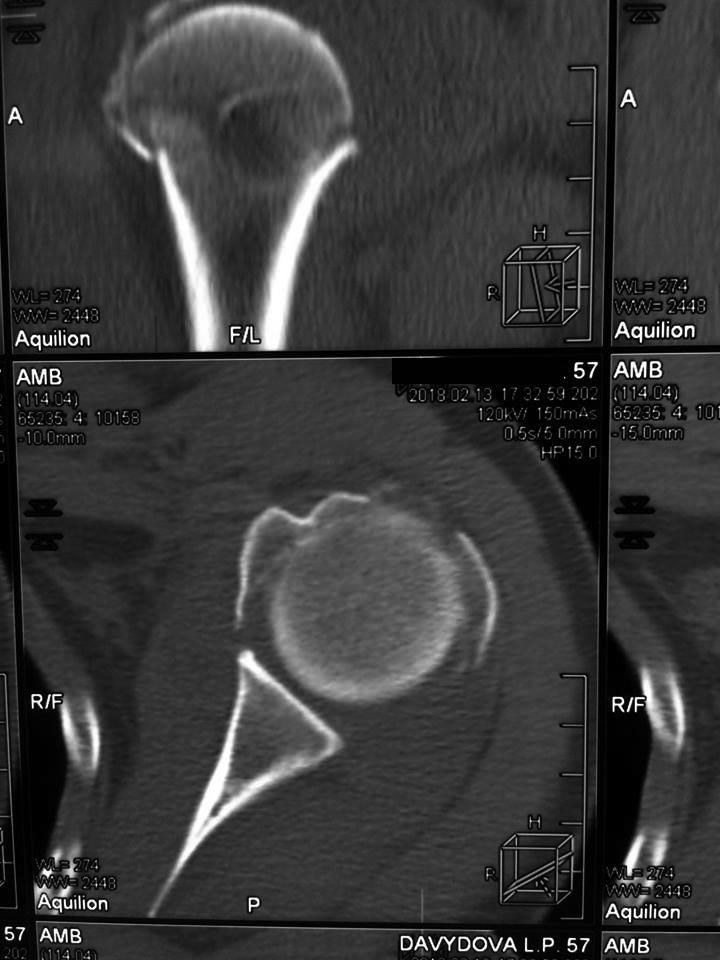

[Ortho] Перелом проксимального метаэпифиза плеча

Дорогие коллеги! Мнение о тактике лечения пациентки в нашем отделении

разделилось.

травма 10 дней назад, падение при катании на обычных лыжах. Сама

врач-рентгенолог 57 лет.

Левая рука, недоминатная. На данный момент ходит в косынке, вся в

сомнениях, что делать.

Мнения по лечению: - ничего не делать - остеосинтез пластиной

блокированной - первичное эндопротезирование (в наличие только геми,

delta не потянет) Может кто-то что более дельное предложит.